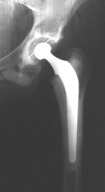

In osteonecrosis, it often comes down to a decision for replacement of the damaged tissue of the hip. The artificial components of the hip come in two basic types; the acetabular component (or hip socket portion) is designed to replace the natural acetabulum, while the femoral component (or hip stem portion) will replace the pivoting femoral head. Diseased bone may be replaced with a wide variety of materials, including other pieces of bone, shaped metal, polyethylene, or even ceramic held in place either with or without forms of cement.

A completely artificial replacement of the damaged joint, known as a joint prosthesis, is classified as a Total Hip Arthroplasty or simply Total Hip. This means that the articular surfaces of the acetabulum and the femur are replaced.

Patients who have more extensive hip procedures get up and around after surgery faster because more diseased bone is replaced. After Osteotomy, protected weight bearing can be initiated soon after surgery and continues for the first six weeks of recovery. After that interval, as that person is able, full independent ambulation can be gained. With arthroplasty, including Total Hip Arthroplasty, weight bearing can resume immediately after surgery, taking into account surgeon preferences and that person’s individual considerations.

Later risks associated with total hip surgery include the possibility that the prosthetic device may loosen from the bone and that late infections or dislocations may occur. However, numerous studies have shown that a technically well-performed total hip replacement is more than 90 percent likely to be in service and functioning well more than 10 years after the surgery, and some sources report full function in as much as 80 percent 20 years after surgery (Leopold, 2003), (Total Hip Replacement, 2003).